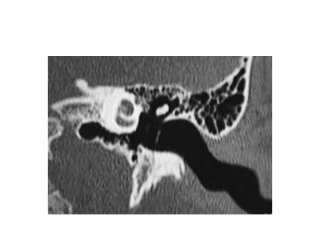

Subcochlear canaliculus type A

Subcochlear canaliculus type B

Subcochlear canaliculus type C

Temporal bone CT. Look at the sub-cochlear canaliculus or sub-cochlear

tunnel that can allow endoscopic transcanal retrocochlear access to the IAC

and drain the petrous apex cells